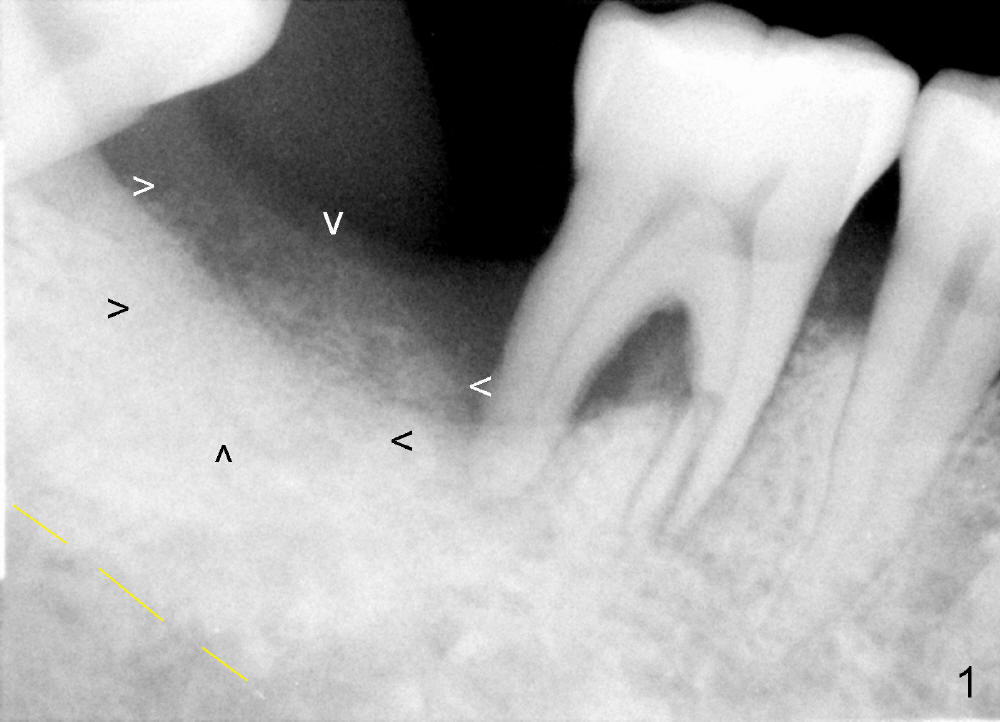

Luckily the patient returns for #31 implantation 4 months post socket preservation. Bone forms in the alveolus and above (Fig.1 black and white arrowheads, respectively). A 6 mm tissue punch is used to open the wound (Fig.2). Osteotomy forms using bone expanders, reamers and taps (Fig.3: 6x14 mm tap). Without infection, local anesthesia is more easily achieved than immediate implant when infection exists. The depth is controlled more readily with delayed implantation. Following adjustment of trajectory, a 7x11 mm implant is placed with insertion torque 60 Ncm (Fig.4 I). Fig.5 shows that the implant obliterates the wound; an abutment (A) is placed to retain perio dressing. With formation of new bone from socket preservation, insertion torque seems to be more easily obtained with the short implant. There is no space to re-use the harvested bone (Fig.6). The implant remains stable postop. Apparent new bone is forming toward the distal coronal threads 5 months postop (Fig.7). The bone around the implant remains stable 17 months post cementation (Fig.8), although there is an episode infection at the neighboring tooth (#30). The patient is more eager to have implants for the maxilla, since the flipper has lost. After implant placement at #7, the pain at #30 becomes more severe.